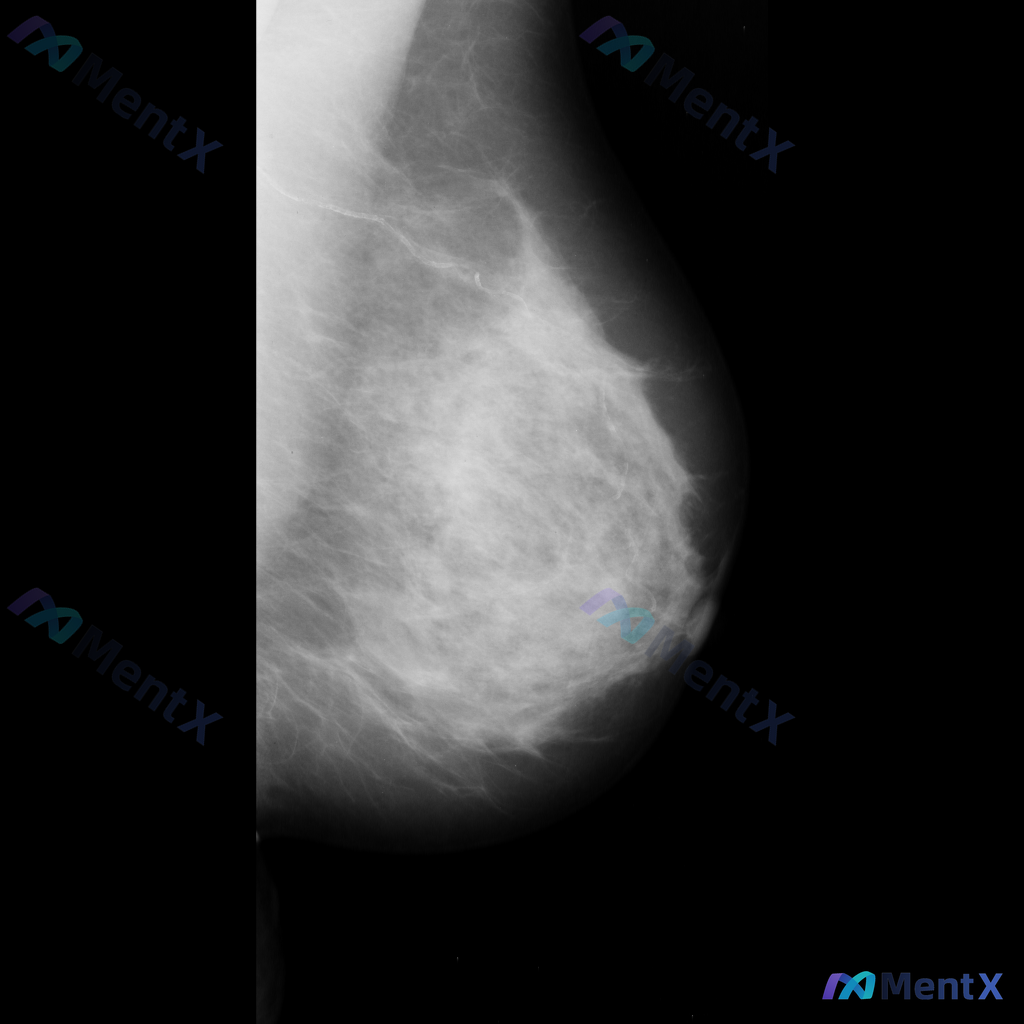

整理到一张乳腺钼靶的影像描述资料,大家帮忙看看这种情况第一反应会怎么评估: - 背景乳腺:多量腺体型或致密型(BI-RADS C或D) - 异常发现:右上象限靠近皮肤边缘处,见散在、细小、点状或线样钙化,部分似有分支样改变,呈局限性分布,部分似沿导管走行 - 目前暂未提供明确的临床病史、既往乳腺影像...